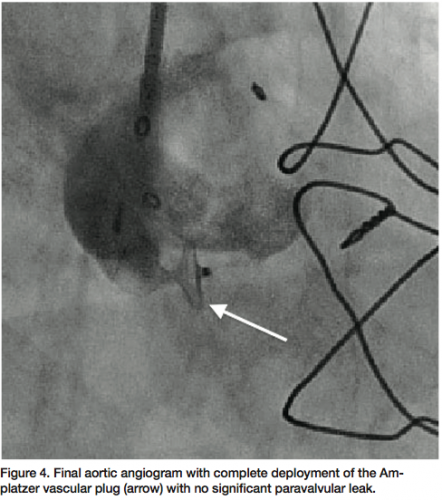

defect (Figure 3). The two proximal lobes of the device were then packed against the aortic side of the defect and with adequate positioning confirmed, the delivery system disengaged and final angiographic (Figure 4) and transesophageal images obtained, demonstrating no significant aortic insufficiency (Figure 5). All catheters and sheaths were removed, with hemostasis achieved using a vascular closure device. The patient was discharged home the following day without any complications.